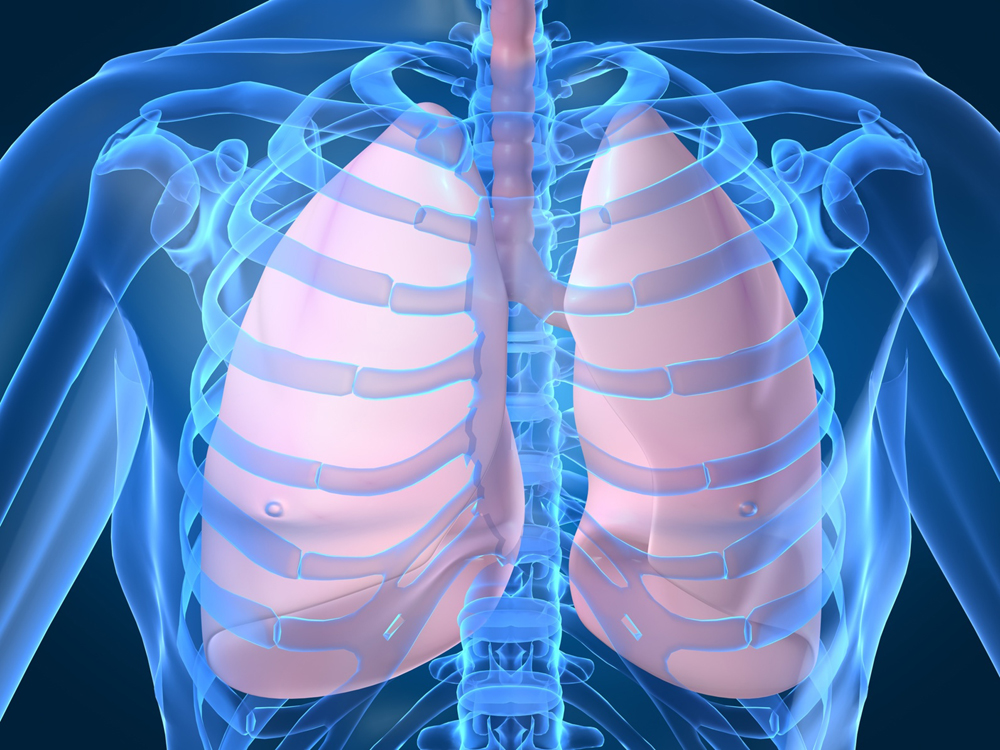

Таинство дыхания: глубокий взгляд на легкие человека в картинках

Раздел: Снимки-откровения